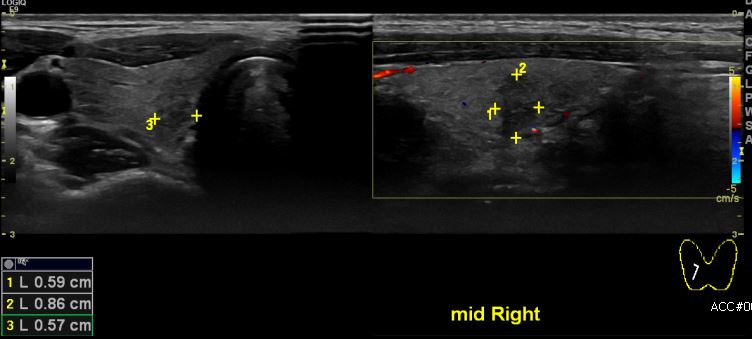

상기환자 갑상선 가족력있어 내원하신 30대 여성분으로 본원 초음파 검사 시행한 결과 우측 갑상선에 의심스러운  0.8cm 결절있어 액상흡인세포병리검사 시행하여  우측 갑상선 유두암 진단 되었습니다.